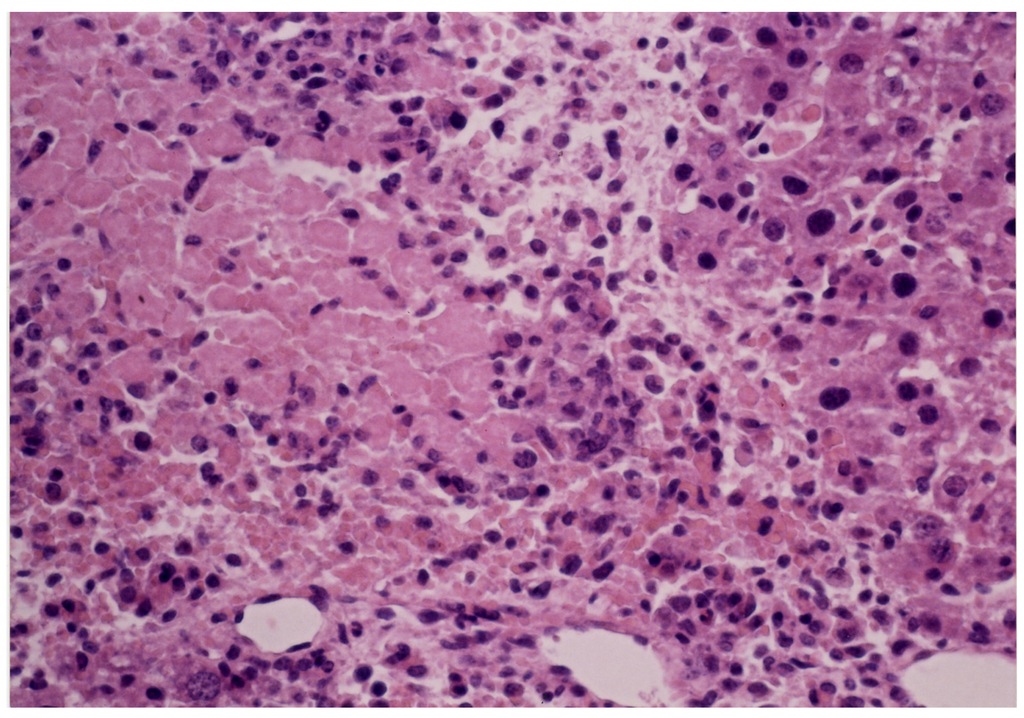

The MLD of carp toxin in mice was estimated to be 2.6 mg/20 g body weight when injected i.p. [21]. The signs observed included paralysis convulsions of hind legs, and other neurological signs. In addition, the LD50 values of 2.5 mg/20 g mouse was reported [32]. During intraperitoneal administration at every 24 h, with a dose of 1.0 mg, some mice died on approximately the fifth day. All of the toxin-administered mice exhibited the well-documented signs of carp poisoning, such as ataxia due to paralysis, convulsions of hind legs, and nervous disorder, before death. On the 4th day after administration of the toxin, the level of BUN increased from the initial value (16.5 ± 1.85 mg/dL) (mean ± S.D., n = 5) to 22.88 ± 3.18 mg/dL, indicating the dysfunction of kidney. However, mice administered with physiological saline revealed no pathological signs, and did not exhibit any signficant change in BUN level. Patients suffering due to ingestion of grass carp and/or carp gallbladders commonly developed edema and oliguria, followed by gastrointestinal symptoms, such as abdominal pain, nausea, vomiting, and watery diarrhea [2,4,5,6,7,8,9,10,11]. In most of the cases, liver dysfunction and azotemia, with a remarkable increase of BUN, were observed. Increase of BUN in the toxin-administered mice could account for acute renal failure in human patients. Liver biopsy from the mouse administered with carp toxin revealed necrosis of hepatocytes and infiltration of neutrophils (Figure 9), whereas biopsy of the control mouse liver indicated no significant changes at all. This observation image revealed findings consistent with acute toxic hepatitis. In many cases of poisonings due to ingestion of gallbladders of cyprinid fish, blood chemistry showed elevation of BUN, creatinine, ALT, and aspartate aminotransferase (AST) (formerly glutamic oxaloacetic transaminase (GOT)). Owada et al. [10] reported two poisoning incidents, in which patients suffered from kidney and liver dysfunctions after ingesting raw carp gallbladder. In addition, their liver biopsies revealed a mild hepatic cell cholestasis.

Figure 9.

.Light microscopy (×245) of the liver from the mouse administered with the carp toxin. The tissue of liver was fixed with 10% neutral buffered formalin. Paraffin sections of 2 μm thickness were prepared and stained with haematoxylin and eosin.